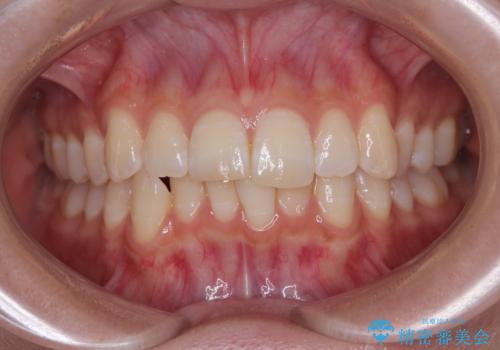

- 上下前歯の重なりを気にして来院された患者様です。

安価なインビザラインパッケージを用いての治療を希望されており、デコボコの程度が中等度であったため、インビザライン・モデレートを用いて矯正治療を行うこととしました。